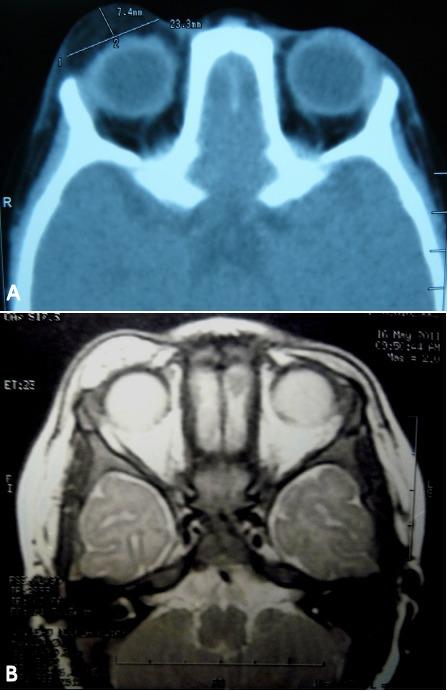

An 18-months-old male infant presented with a rapidly growing tumor on the right upper eyelid. Orbital computed tomography (CT) revealed a large, well-circumscribed mass with low density signal in the right upper eyelid. Magnetic resonance images (MRI) showed a lesion of mixed T1-signal intensity and high signal intensity in T2-weighted images. The tumor was treated by simple anterior orbitotomy with excisional biopsy, and the diagnosis of fibrolipoma was made by histopathologic examination. There was no evidence of tumor at the four-year follow-up. Fibrolipoma is one of the rare variant of the lipoma and only four cases have been reported in the orbit including the present case. Except for this case all other cases were reported in adults.

一名18个月大的男婴因右上眼睑出现迅速生长的肿瘤前来就诊。眼眶计算机断层扫描(CT)显示右上眼睑有一个大的、边界清晰的肿块,呈低密度信号。磁共振成像(MRI)显示在T1加权图像上病变信号强度混合,在T2加权图像上呈高信号强度。该肿瘤通过单纯前路眼眶切开术及切除活检进行治疗,组织病理学检查诊断为纤维脂肪瘤。四年随访时未发现肿瘤迹象。纤维脂肪瘤是脂肪瘤的罕见变体之一,包括本病例在内,眼眶内仅报告过4例。除本病例外,其他所有病例均报告于成人。